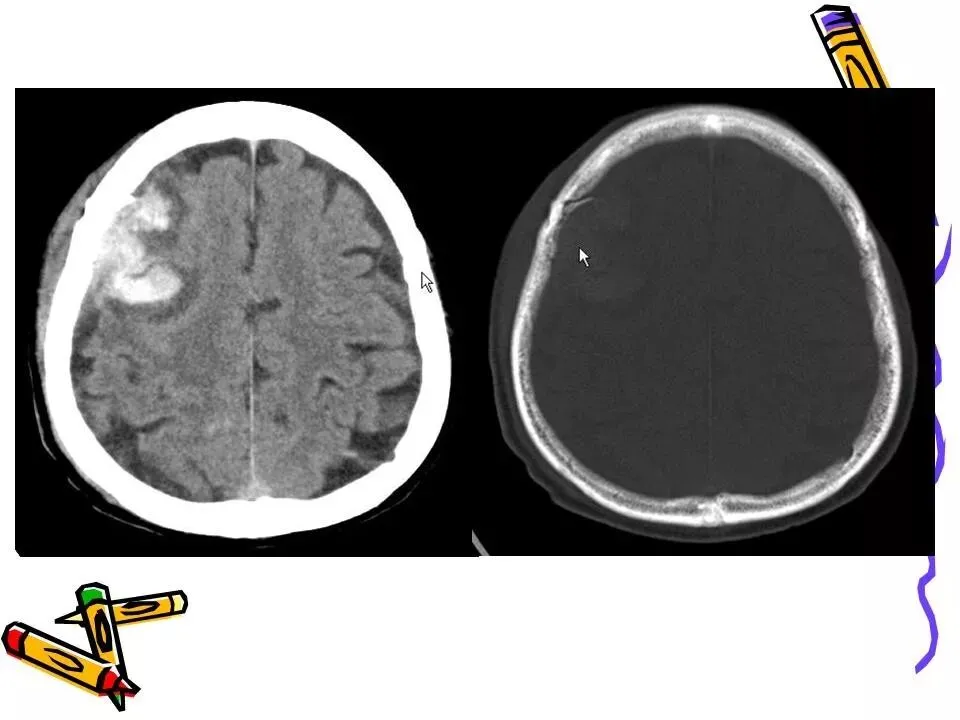

>常见颅脑外伤CT诊断(PPT)

常见颅脑外伤CT诊断(PPT)